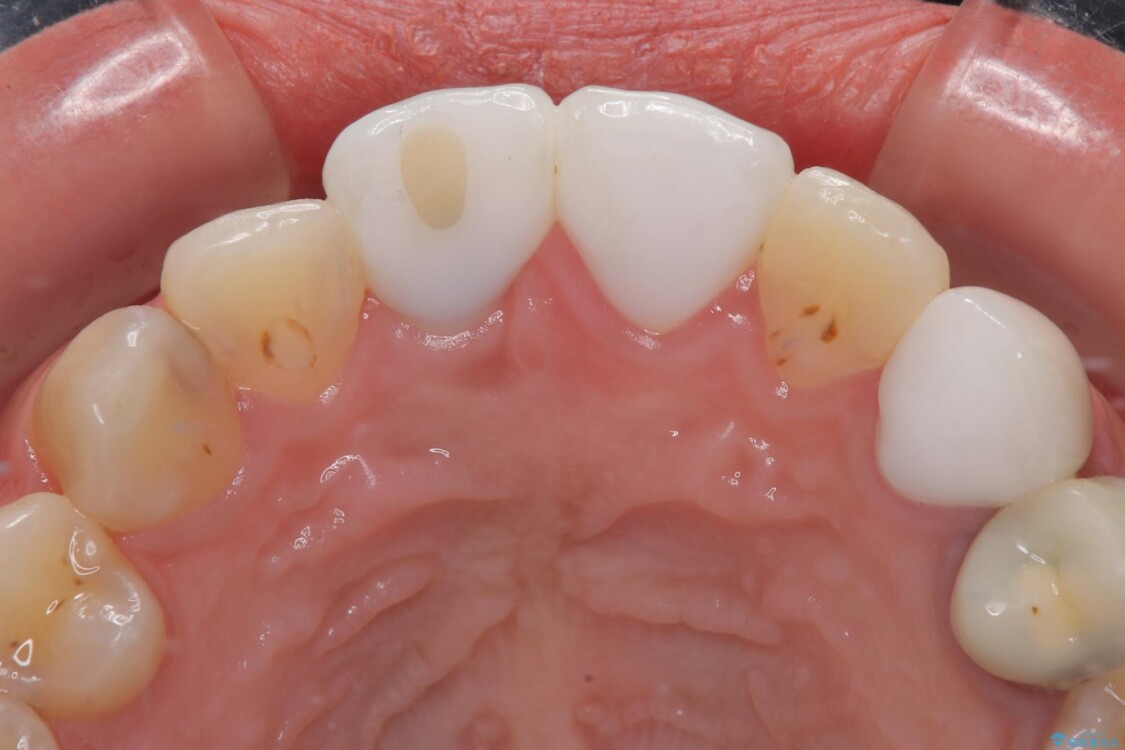

治療前

• 「抜歯してブリッジ」と言われた20代女性が選んだ治療とは|たった4か月で自然な笑顔に抜歯即時インプラント+審美補綴の症例 治療前画像